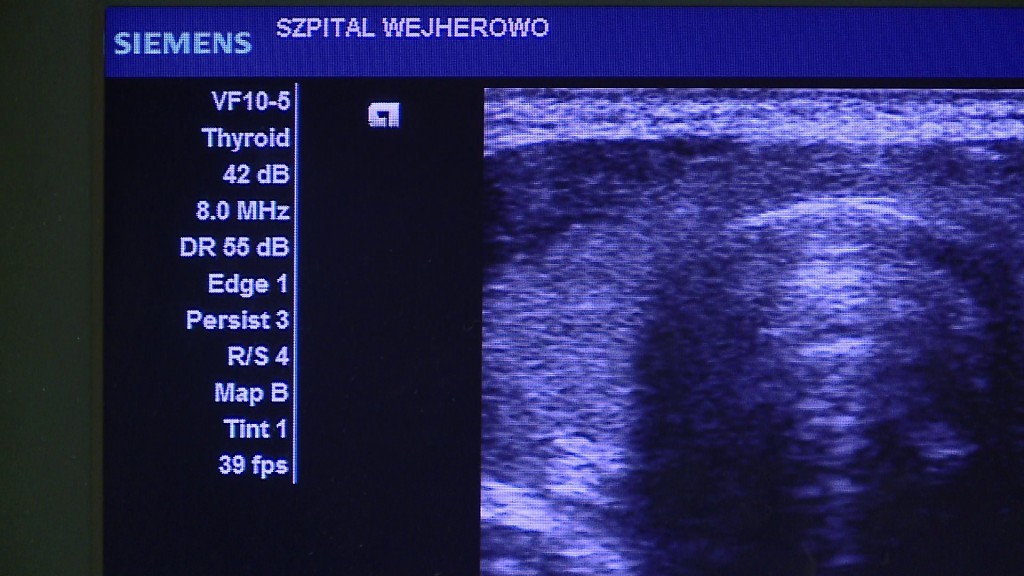

W poniedziałek (7 maja) w Szpitalu Specjalistycznym im. F. Ceynowy w Wejherowie zawarto umowę dotacyjną na zakup nowego aparatu USG. Miasto przekazało placówce na ten cel 50 tysięcy złotych. Dokument podpisali: Arkadiusz Kraszkiewicz, wiceprezydent Wejherowa, Jolanta Sobierańska-Grenda, prezes spółki Szpitale Pomorskie i Andrzej Zieleniewski, wiceprezes Szpitali Pomorskich.

Nowy ultrasonograf, którego koszt jest szacowany na 90 tysięcy złotych, ma trafić na Oddział Chirurgii Ogólnej i Onkologicznej wejherowskiego szpitala. Każdego roku jest tam leczonych około cztery tysiące pacjentów. Lekarze przeprowadzają rocznie 2500–3000 zabiegów.

Są to zabiegi w obrębie jamy brzusznej, tarczycy, chirurgiczne, również konieczne ze względów urazowych – wyjaśnia dr n. med. Mieczysław Witzling, ordynator Oddziału Chirurgii Ogólnej i Onkologicznej Szpitala Specjalistycznego im. F. Ceynowy w Wejherowie. – Przy tylu leczonych i operowanych chorych, w tej chwili wymagana jest staranna i nowoczesna diagnostyka. Ten sprzęt nam ją zapewni, ponieważ dzięki aparatom do diagnostyki obrazowej, jesteśmy w stanie oceniać postęp leczenia, a także wykrywać powikłania. Co najważniejsze, przy takiej liczbie pacjentów taki sprzęt powinien być zawsze dostępny dla lekarza – podkreśla.